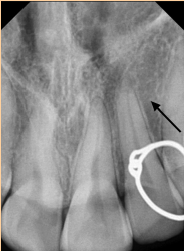

28. What is showing by arrow?

29. What is shown by the arrow?

30. What is shown by arrow C?

31. What arrow shows?

32. What is showing by the arrow?